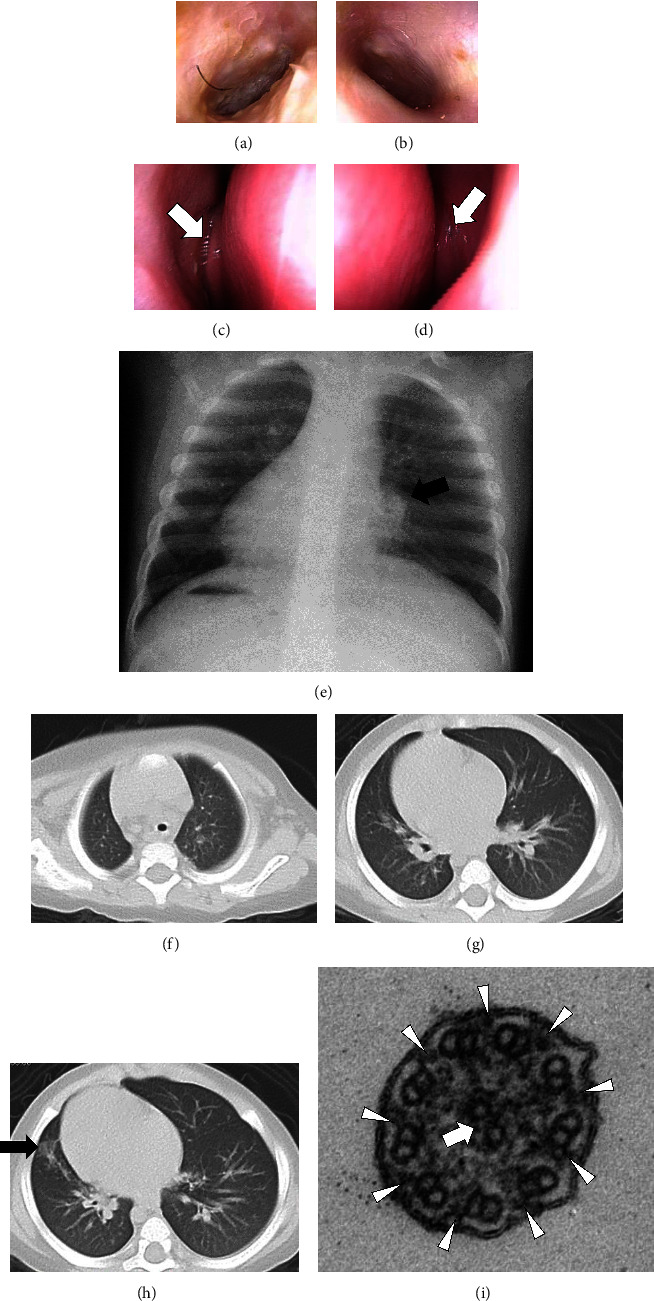

原发性纤毛运动障碍(PCD)是一种由纤毛运动相关基因引起的遗传性疾病。我们报告了两例由 OFD1 中心粒和中心极卫星蛋白(OFD1)基因半杂合子致病变体引起的 PCD 男性儿科病例。变异基因为 NM_003611.3:病例 1 中的 c.[2789_2793delTAAAA] (p.[Ile930LysfsTer8]) 和病例 2 中的 c.[2632_2635delGAAG] (p.[Glu878LysfsTer9]) 。两个病例都有反复呼吸道感染的特征。我们发现了一个变异体(c.2632_2635delGAAG),以前从未在任何 OFD1-PCD 病例中报道过。

Primary ciliary dyskinesia (PCD) is a hereditary disease caused by genes related to motile cilia. We report two male pediatric cases of PCD caused by hemizygous pathogenic variants in the OFD1 centriole and centriolar satellite protein (OFD1) gene. The variants were NM_003611.3: c.[2789_2793delTAAAA] (p.[Ile930LysfsTer8]) in Case 1 and c.[2632_2635delGAAG] (p.[Glu878LysfsTer9]) in Case 2. Both cases had characteristic recurrent respiratory infections. Neither case had symptoms of oral-facial-digital syndrome type I. We identified a variant (c.2632_2635delGAAG) that has not been previously reported in any case of OFD1-PCD.